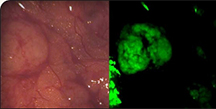

On Target compound OTL38, a product of On Target Laboratories LLC is a novel compound that binds with diseased tissue present in several cancers, making it light up, or fluoresce, during cancer surgery. (On Target Laboratories LLC photo) Download image

On Target’s lead compound, OTL38 is a novel compound that binds with diseased tissue present in several cancers, making it light up, or fluoresce, during cancer surgery. The compound aims to help surgeons pinpoint and more accurately remove cancerous tissues while preserving healthy tissue in patients.